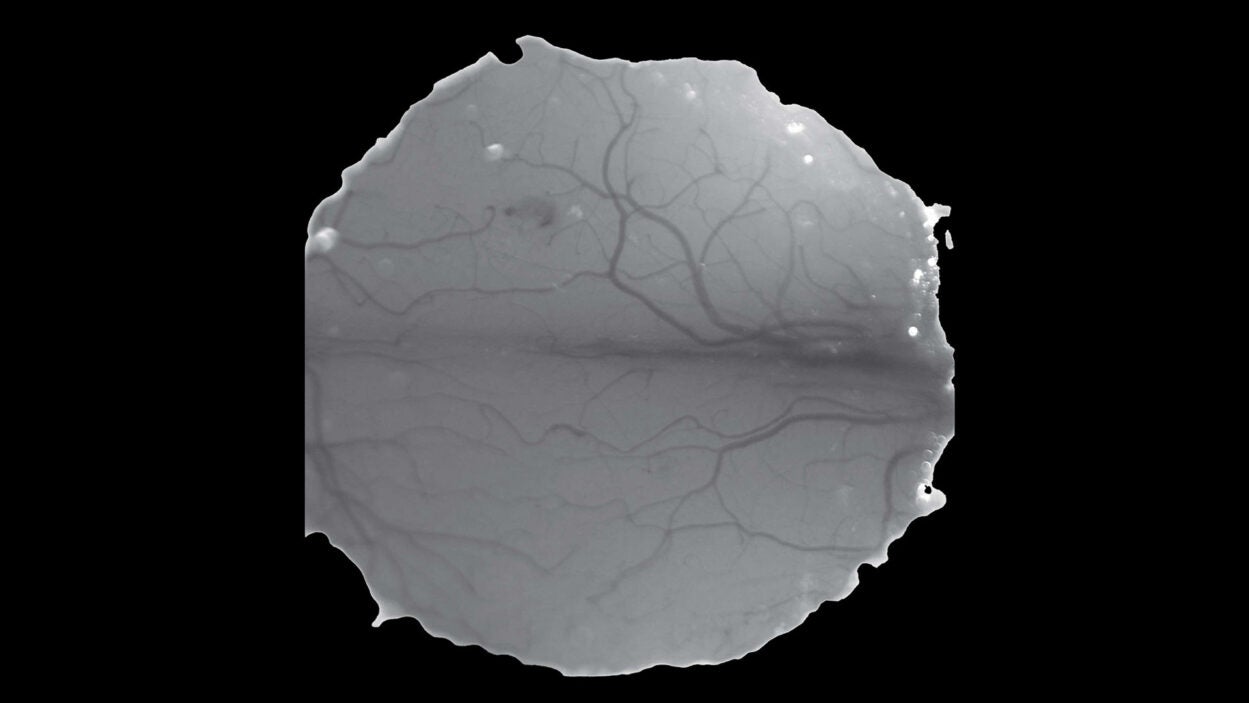

Stunning new images from CSHL’s Joshua-Tor lab reveal how the protein complex interacts with differently shaped primary microRNAs. Read the story »

The brain relies on cells called OPCs to refine neural connections. CSHL’s Lucas Cheadle can now look at these synapse pruners in a whole new light. Read the story »

That’s not the Starship Enterprise burning up in space. It’s an up-close look at precancerous pancreatic lesions and the mucus they produce. Read the story »